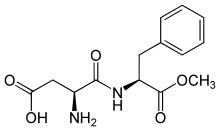

| IUPAC name

Methyl L-α-aspartyl-L-phenylalaninate | |

| Other names

N-(L-α-Aspartyl)-L-phenylalanine, 1-methyl ester | |

| C14H18N2O5 | |

Aspartame is a methyl ester of the dipeptide of the natural amino acids L-aspartic acid and L-phenylalanine.[4] Under strongly acidic or alkaline conditions, aspartame may generate methanol by hydrolysis. Under more severe conditions, the peptide bonds are also hydrolyzed, resulting in free amino acids.[50]